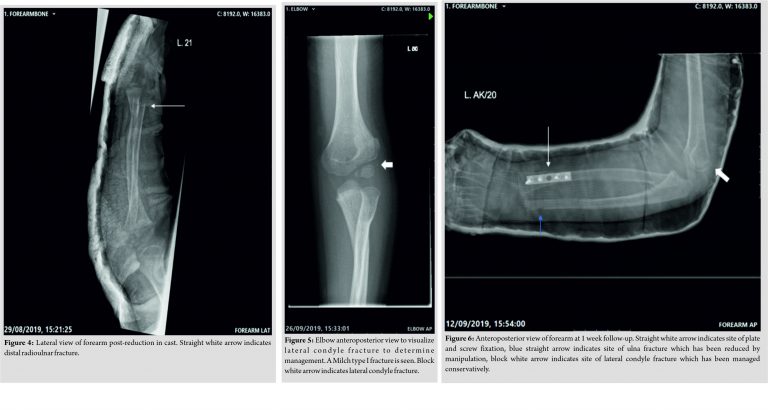

The patient was initially managed emergently in an above elbow plaster cast (Fig. 3, 4), with elevation and monitoring for any neurovascular compromise. Computed tomography (CT) imaging was performed to completely assess the fracture pattern and for discussion with our local regional trauma center. CT images revealed Milch Type I fracture; the CT image is poor due to image distortion caused by plaster; hence, an X-ray of the elbow is showed instead (Fig. 5). Given the minimal displacement of the lateral condyle, a conservative course of management was decided on for this. Intraoperatively, an initial attempt to perform a closed reduction of the distal radius and ulna was made but this was unsuccessful. The fracture was not amenable to K-wire fixation due to its diaphyseal-metaphyseal location and so open reduction internal fixation was performed, with a 5-hole Marquardt low profile third tubular plate to achieve anatomical fixation. On table image, intensification was used to confirm congruity and stability of the radiocapitellar joint and radioulnar joints. The angulated midshaft fracture of ulna was manipulated into an anatomical position and an above elbow plaster cast was applied to maintain the minimally displaced position of the lateral epicondyle fracture.

The child remained in an above elbow plaster cast for 4 weeks. On immediate removal of the plaster, elbow range of movement (ROM) was from 40 to 100°. A 80° of pronation was retained, but supination was restricted to 20°. No neurovascular deficit was identified and X-rays demonstrated good fracture union (Fig. 6, 7). At the 8 weeks post-operative follow-up, elbow ROM further improved, with almost full extension, 120° flexion, 70° of pronation and supination passively but achieving 90° actively on pronation and supination. By 12 weeks after surgery, there was a full ROM of the elbow, wrist, and forearm with complete radiological union (Fig. 8, 9). At 13 weeks post-injury, the plate was removed uneventfully and at 2 weeks after the procedure, his wound was well healed, and limb was neurovascularly intact with a full ROM of his elbow, wrist, and forearm at which point he was discharged from our care.